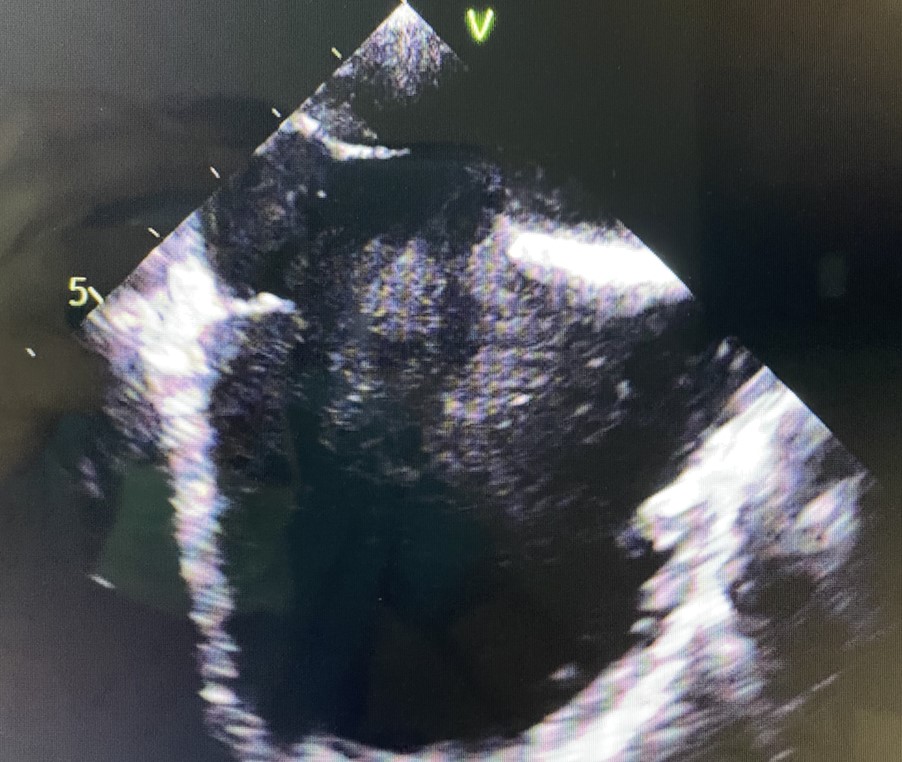

Transesophageal Echocardiogram showing large ASD